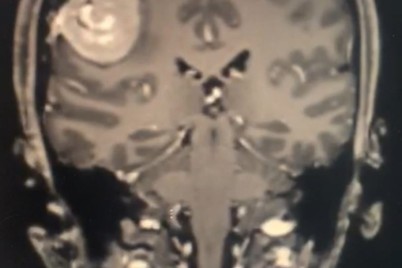

الطائف - هلال اليزيدي أنهى فريق من جراحة المخ والاعصاب بمجمع الملك فيصل بالطائف معاناة سيدة من "صداع مزمن"...